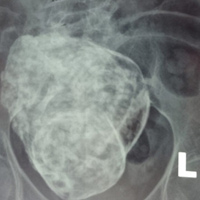

Thế giới chỉ ghi nhận 300 trường hợp Bác sỹ CKII Lê Quang Vinh cũng cho biết thêm, bình thường khi thai bị chết lưu sẽ tìm cách tự đào thải ra khỏi cơ thể mẹ hoặc bằng các biện pháp nạo hút, bác sĩ sẽ lấy thai lưu ra ngoài. Trong trường hợp này, cụ già 76 tuổi đã qua tuổi sinh sản từ lâu, vì thế việc phát hiện thai nhi bị vôi hóa phải qua các xét nghiệm và chẩn đoán hình ảnh. Ðây là ca bệnh hiếm gặp, y văn thế giới mới phát hiện khoảng 300 trường hợp. Ở ca bệnh đặc biệt này, các bác sĩ sẽ thăm khám, làm các xét nghiệm cần thiết và quan trọng nhất là tùy vào tình hình thể trạng của bệnh nhân để có cách xử trí thích hợp. |

Ngày bà nhập viện Đa khoa Cam Ranh, các bác sĩ chẩn đoán cơn đau bụng âm ỉ của bà bắt nguồn từ cái bào thai đã hóa thạch. Hôm đó, ngồi trong phòng khám “nuốt” từng lời bác sĩ, bà Thập thấy chẳng khác nào sét đánh ngang tai. Thì ra gần 30 năm đằng đẵng vừa qua, bà mâng trong người một mầm sống. Bà Thập cười cho biết: “Lúc chồng tôi còn sống, chúng tôi vẫn “nồng nàn” với nhau lắm. Nếu theo các y bác sỹ thông báo thì hồi ấy tôi thụ thai cũng đã suýt soát 50 tuổi rồi. Ở cái tuổi ấy mà vẫn có thai được thì cũng là chuyện lạ! Kỳ lạ hơn nữa là suốt mấy chục năm qua, nó vẫn ở trong người tôi mà tôi không hề hay biết gì!”

Trên thế giới cũng từng có trường hợp như thế, chứ đâu phải chỉ riêng mẹ tôi”. Người dân trong vùng rất tò mò và muốn thử một lần nhìn thấy thai đá cho biết. “Đời tôi chưa từng nghe nói đến chuyện thai đá bao giờ và cũng càng chưa từng nghĩ đến chuyện bà Thập lại mang thai đá, tôi rất muốn nhìn xem thai đá trông ra sao? Không có ý gì xấu mà chỉ thấy hiện tượng đặc biệt hiếm gặp thôi!”, một người đàn ông trong bệnh viện bày tỏ. Không giống với các thai phụ khác, theo dự đoán, sau khi “chào đời” thai nhi của bà Thập sẽ giống một tảng đá có hình người, dù kích cỡ không lớn lắm.

Trên thực tế có những trường hợp thai chết lưu không tìm thấy nguyên nhân, nhưng y học ngày nay đã biết nhiều nguyên nhân gây ra thai chết lưu. Với những thai phụ tuổi cao trên 40 tuổi, tỉ lệ này cao gấp 5 lần so với nhóm những người mẹ dưới 40 tuổi. Việc bà Thập còn thụ thai được ở độ tuổi 50 cũng là một điều ít gặp. Thêm nữa, việc thai đá này không làm ảnh hưởng tới sức khỏe, cũng như vận động, và bà không hề hay biết sau từng ấy năm quả là một sự kiện hy hữu của y văn. Sau sự việc hi hữu này, bà Thập chỉ mong muốn các y bác sỹ sớm tiến hành giải quyết bào thai đá này, để sức khỏe của bà được ổn định, cũng như tâm lý không còn lo sợ nữa.